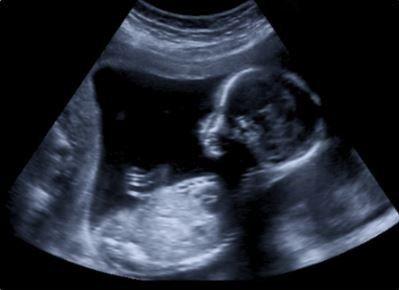

El Partido Nacional Eslovaco (SSN) ha presentado un proyecto de ley para prevenir la práctica del aborto, que incluye tres medidas esenciales: la prohibición del aborto, así como la obligación de mostrar a las mujeres embarazadas la ecografía del feto y de hacerle escuchar los latidos del corazón del feto, según iinforma el periódico Slovak Spectator.

Por lo tanto, los médicos deben mostrar a la mujer que desea abortar una imagen ecográfica ¨de la etapa de desarrollo del embrión o feto cuyo desarrollo debe interrumpirse¨ y ¨si esto es técnicamente posible, el médico también debe permitir que se escuchen los latidos del corazón del embrión o el feto¨, según el proyecto de ley.